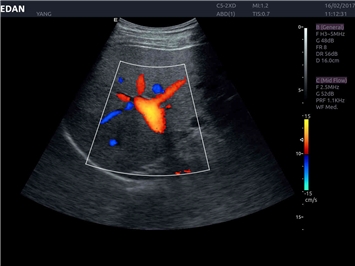

• Кардиологических исследований

Трехмерная реконструкция ЦДК:

Да

Тканевой допплер:

Триплексное сканирование: